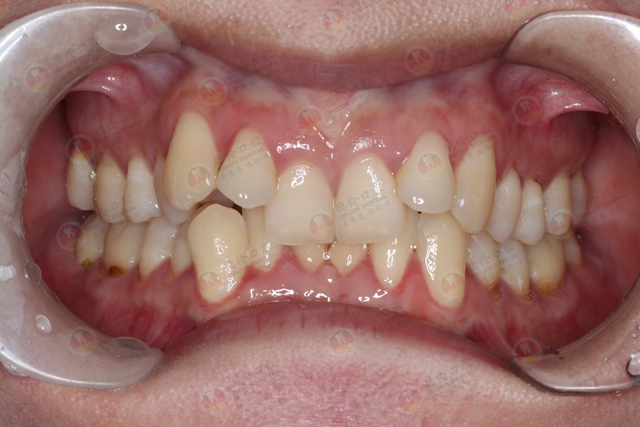

03、牙列不齐

牙齿排列不整齐,会造成刷牙的时候很难刷干净,这就会导致菌斑和软垢残留,引发牙周组织的一系列问题,其中也就包括了牙龈萎缩。